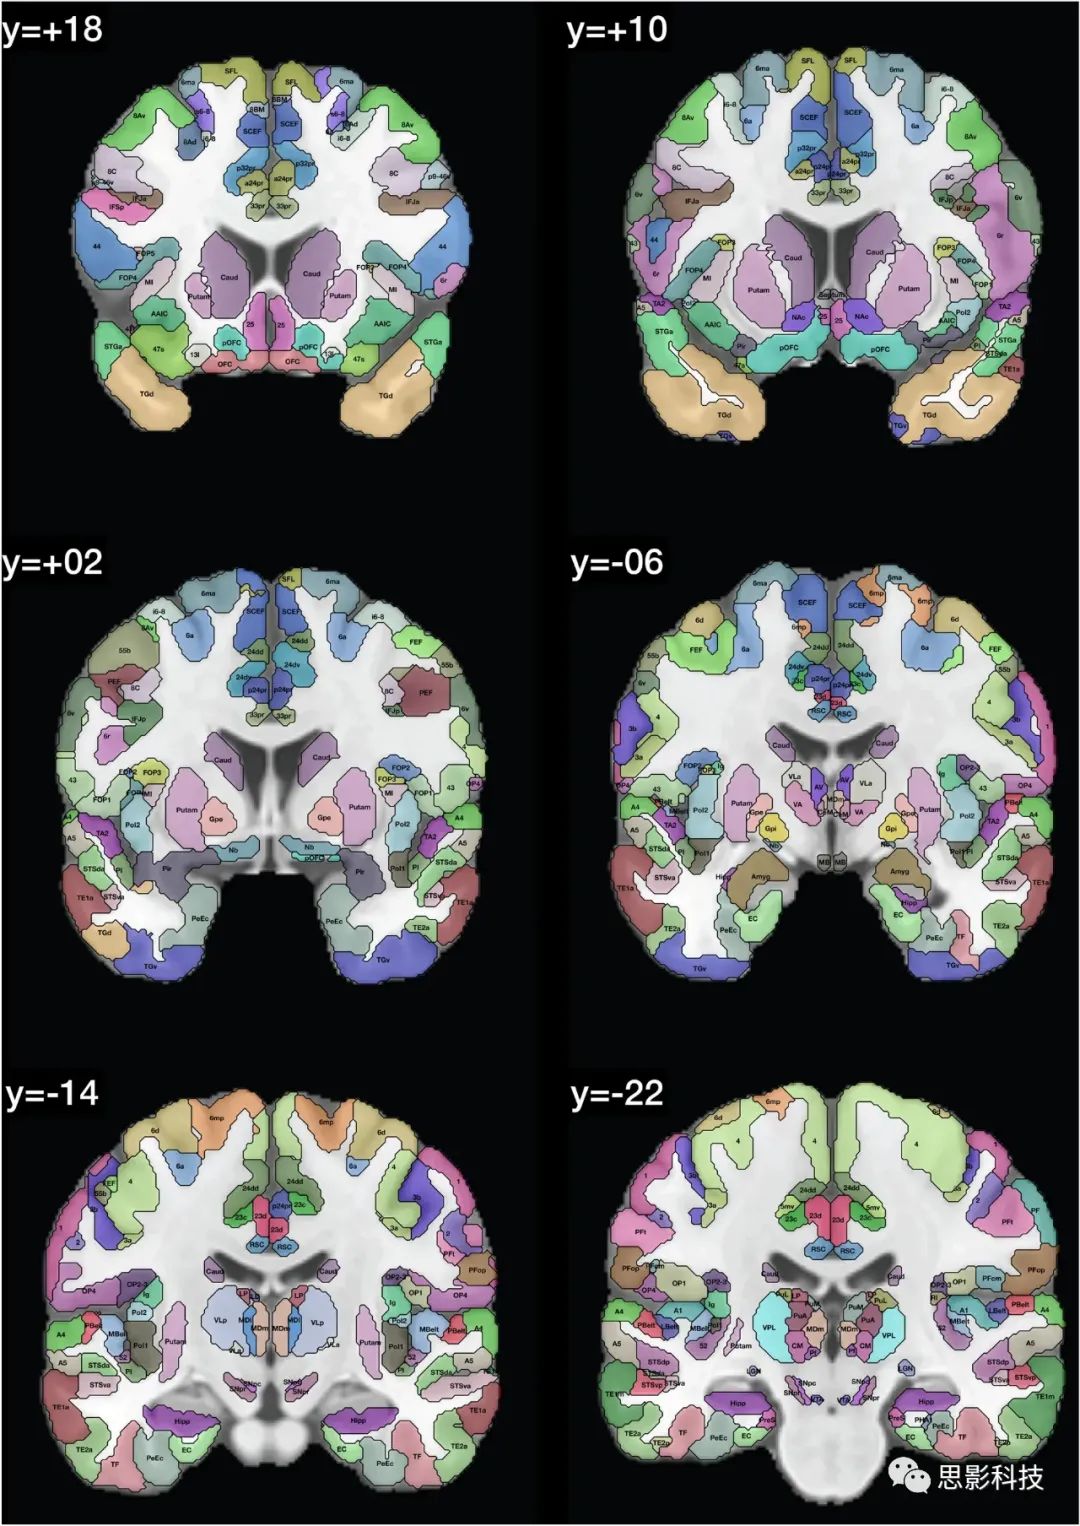

在人类连接组计划(HCP)图谱中区域的定义显示在Glasser et al.(2016a, b)的Glasser_2016_Table.xlsx中。这些区域的列表提供在表1中,并且在图1中,我们展示了带有在HCPex图谱中定义的区域标签的冠状切片。图1中的皮层区域是按照人类连接组计划(HCP)图谱(Glasser et al. 2016a)中的定义来的。

图1:展示了HCPex图谱中定义的区域和新增的皮层下区域的示例冠状切片。这些切片中使用的缩写与表1中的相同。这些冠状切片的y轴坐标是根据MNI(蒙特利尔神经学研究所)坐标系统来确定的。

图1提供了扩展HCP图谱的标记版本,以帮助读者识别这些人脑冠状切片中的脑区域。值得注意的是,一些小的脑结构在这些冠状切片中可能显得非常小,因为它们是被8毫米分隔开的(例如隔核就位于MNI坐标y:3–10之间)。表1和表2提供了图谱中脑区域的列表。在这个重新排序的列表中,标签列表提供在HCPex_LabelID.mat中。

本文描述的HCPex图谱扩展了HCP-MMP1图谱(Glasser et al. 2016a),通过增加66个皮下区域,以体积(volume)形式提供以适用于多种类型的神经影像软件,包括SPM,提供带标签的大脑冠状切片以清晰可视化HCPex图谱中定义的皮层和皮下区域(图1),并提供图谱中皮层区域的可选重排序(表1)。我们已经发现,有了这些扩展,HCPex图谱非常有帮助(Huang et al. 2021; Ma et al. 2021; Rolls et al. 2021)。

总之,这里描述的HCPex图谱通过增加66个皮层下区域、以体积(Volume)形式提供以适用于多种类型的神经影像软件(包括SPM)、提供带标签的大脑冠状切片以清晰可视化HCPex图谱中定义的皮层和皮层下区域(图1)以及提供图谱中皮层区域的可选重排序(表1),从而扩展了HCP-MMP1图谱(Glasser et al. 2016a)。